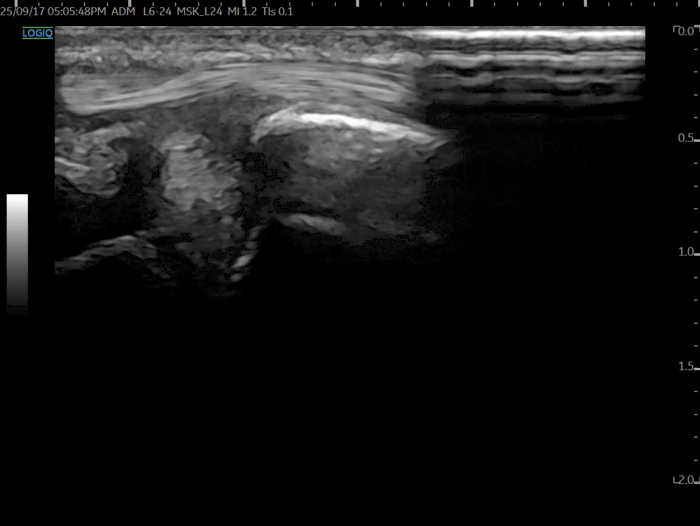

TFCC, 초음파로 보면?

2018년부터 TFCC를

초음파로 스캔하는 임상 연구들이

대거 쏟아지고 있습니다.

@ DOI: 10.3390/jcm8101540

민트색 박스 표시한

척골 경상돌기(Sp)에 프로브를 대고

TFCC 장축 스캔을 하면요.

가장 바깥에

척측수근신근 힘줄이 보이고요.**

(ECU, extensor carpi ulnaris)

잘 보이시진 않겠지만

힘줄집(subsheath)을

신전근 지대(Extensor retinaculum)가

감싸고 있는 형태입니다.

MRI상 삼각섬유연골 파열로

진단 받으신 분들은

표준 경혈 초음파와 달리이렇게까맣게 손상된 틈이 보이는데요.

제가 1억이 넘는 GE초음파 최상위 기종

LOGIQ FORTIS를 쓰고 있는데

사람에 따라서

요골 부착부나 척골 부착부쪽은

안 보일 때가 있습니다.

양방 초음파든 한방 초음파든

삼각섬유연골의 전체 범위를 볼 수 없어서

확실하게 진단할 순 없고요.

반드시 MRI를 찍어봐야 합니다.

초음파는 개인 의원급에서

일차적으로 확인하는 목적이 크고요.

MRI 검사를 바탕으로

주사 놓을 때 가이드 목적으로

초음파를 사용하는 겁니다.